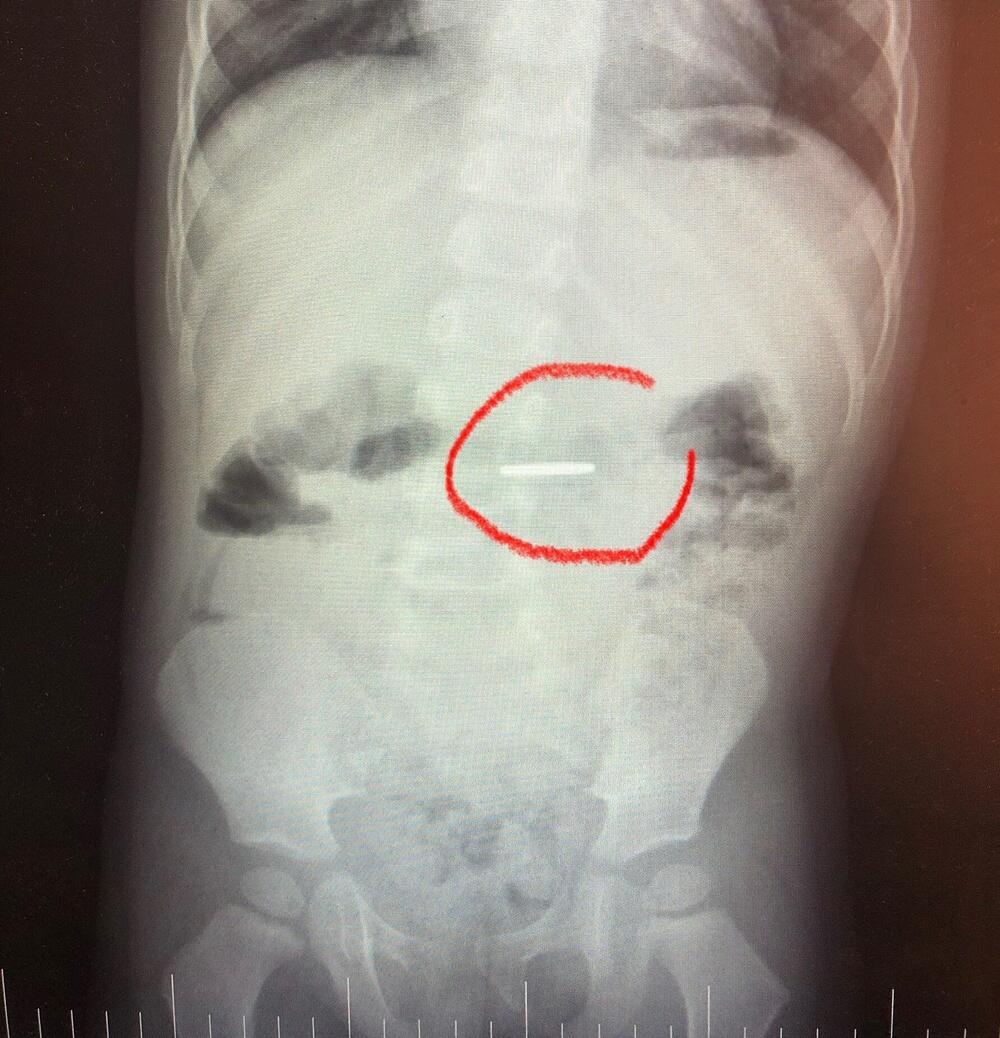

Врачи воронежской ОДКБ № 2 показали рентгеновские снимки детей, которые проглотили инородные предметы. Это и канцелярские кнопки, и батарейки, а также магниты, шурупы, гайки и прочее.

В Воронежской области участились случаи проглатывания детьми инородных предметов. Это связано с тем, что в летний период малыши чаще бывают в песочницах и на игровых площадках, где могут затащить в род все, что попало.